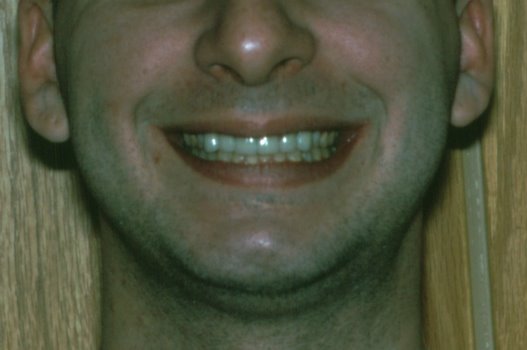

Not only

did this patient have a cavity problem, but he also grinds his teeth at

night causing an extreme amount of wear. A previous dentist had tried

to place a couple of crowns (caps), but the end result was two very

short, unappealing teeth. We opened the patient's bite with a

mouthpiece and erupted the back teeth with orthodontic rubber bands.

This provided enough space to construct teeth with the proper length.

And what an awesome result! |